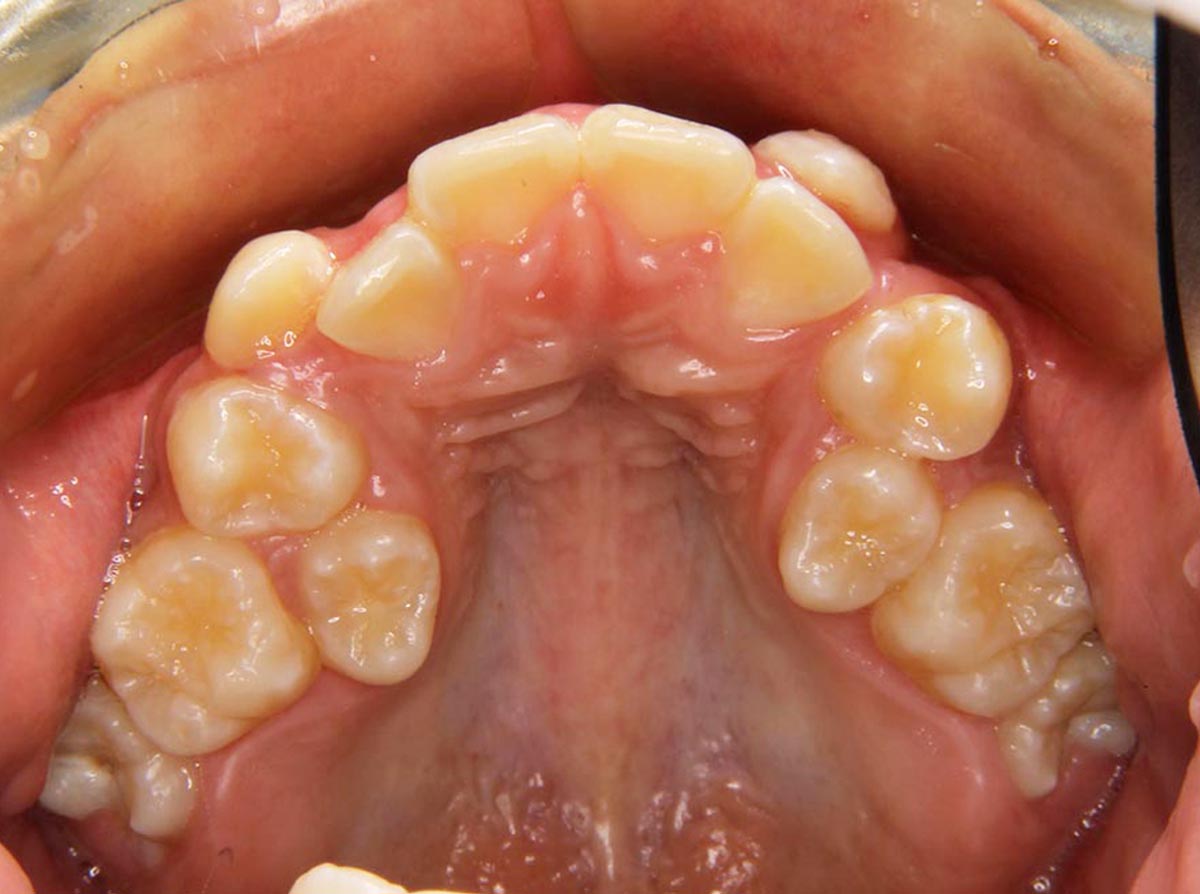

叢生(デコボコ)症例

●主訴

歯のデコボコが気になる

●診断

AngleⅠ級・前歯部叢生

●治療に用いた主な装置

上顎にリンガルブラケット矯正装置、下顎にマルチブラケット装置(ハーフリンガル)

●抜歯部位

非抜歯

●治療期間

2年10ヶ月

●治療費用

約108万円(ともに税込、調整費、保定費まで含む総額制)

●付記

歯列が狭かったので、拡大してから非抜歯で矯正しました。リスクとして、

①歯根吸収…今回は全くありませんでした。

②カリエス(むし歯)…今回は治療途中でむし歯治療を行いました。

③あともどり…保定装置の装着をしっかりしていただいています。